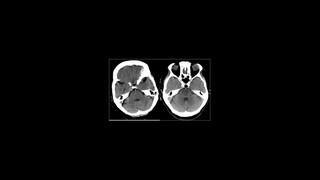

ACV Hemorragico E Izquémico

Lo básico del acv

La clasificación de los hematomas

Parametros de las lesiones cerebrales

Patología craneocerebral